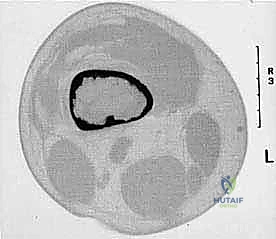

تحديد مراحل الورم (Staging): نظام Enneking

تحديد مرحلة الورم هو الخطوة الأهم قبل أي تدخل جراحي. يعتمد الدكتور هطيف على نظام (Enneking) لتحديد مراحل أورام العظام، والذي يعتمد على ثلاثة عوامل:

1. درجة الورم (Grade - G): بناءً على الفحص النسيجي (G1 منخفض الدرجة، G2 عالي الدرجة).

2. الموقع (Site - T): هل الورم داخل الحيز العظمي (Intracompartmental - T1) أم اخترق القشرة وخرج للحيز الخارجي (Extracompartmental - T2)؟

3. الانتشار (Metastasis - M): هل انتقل الورم لأعضاء أخرى (M0 لا يوجد، M1 يوجد انتشار)؟

مبادئ الاستئصال الجراحي: الهوامش الجراحية (Surgical Margins)

الهدف الأول في جراحة الساركوما ليس فقط إزالة الكتلة المرئية، بل استئصالها مع طبقة من الأنسجة السليمة المحيطة بها لضمان عدم ترك أي خلايا مجهرية. تُصنف الهوامش الجراحية إلى:

- الاستئصال داخل الورم (Intralesional): يتم قطع الورم من الداخل. غير مقبول في الساركوما الخبيثة.

- الاستئصال الهامشي (Marginal): الاستئصال عبر الكبسولة الكاذبة للورم. يحمل خطر عودة الورم (Recurrence).

- الاستئصال الواسع (Wide Resection): وهو المعيار الذهبي. يتم استئصال الورم مع طبقة من الأنسجة السليمة المحيطة به (العضلات، العظام). هذا ما يبرع فيه الدكتور هطيف لضمان الشفاء التام.